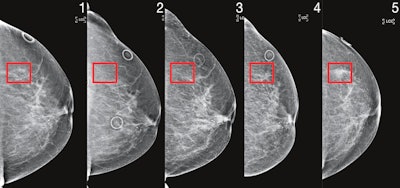

An artificial intelligence (AI) algorithm called Mirai can outperform other risk-assessment models for predicting future risk of breast cancer from a mammogram, potentially enabling earlier identification of high-risk women, according to research published online on 27 January in Science Translational Medicine.

A team of researchers led by Adam Yala, a PhD student in MIT's Computer Science and Artificial Intelligence Laboratory (CSAIL), developed Mirai, a deep-learning algorithm that can estimate a woman's risk of breast cancer across multiple future time points based on analysis of their mammogram and clinical risk factors.